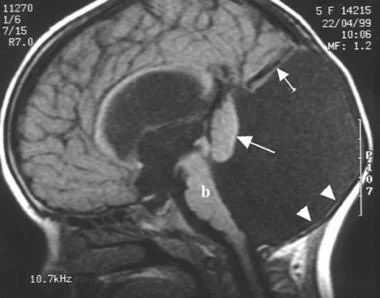

(Слева) МРТ, Т2-ВИ, сагиттальная плоскость. Представлены характерные признаки СЖ: дисгенезия мозолистого тела тонкий перешеек ствола мозга, патологическая ротация червя мозжечка э и затылочное энцефалоцеле.

Признак летучей мыши

На сагиттальных срезах почти всегда отмечается отсутствие червя мозжечка, хотя верхняя его часть (разделенная срединной расщелиной) в ряде случаев присутствует. Своеобразная парциальная гипогенезия червя приводит к появлению специфических формообразующих феноменов IV желудочка: его нижняя часть приобретает треугольноподобную форму, а верхняя благодаря частичной сохранности расщепленного червя — форму «летучей мыши». В нижних отделах задней черепной ямки — ниже гипопластичного червя церебеллярные гемисферы примыкают друг к другу по срединной линии. Верхние мозжечковые ножки не пересекаются в задних отделах среднего мозга и могут быть легко идентифицированы на фоне окружающей их спинномозговой жидкости, будучи позиционированы между средним мозгом и мозжечком. Мост уменьшен в переднезаднем размере (возможно, ввиду отсутствия перекреста пирамид).

Признак коренного зуба